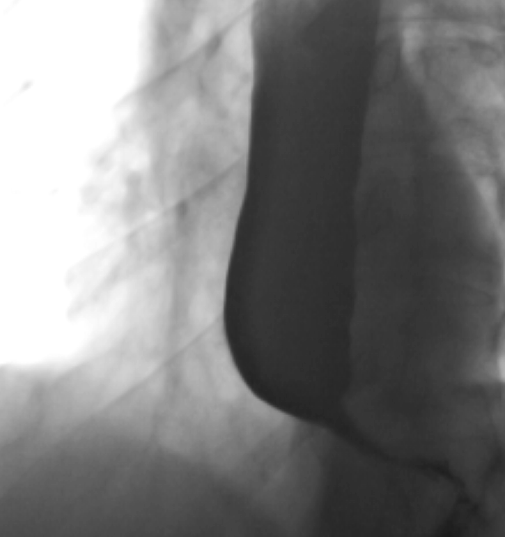

- Dilatation de l’oesophage

- Bec d’oiseau à la jonction Oeso-gastrique